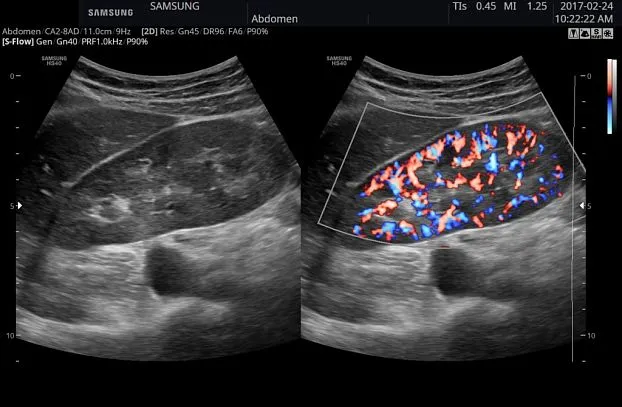

Клинические изображения

- CD — цветное допплеровское картирование с возможностью изменения допплеровского угла.

- PD — энергетический допплер с возможностью изменения допплеровского угла.

- S-Flow — технология цветового допплеровского картирования с повышенной чувствительностью.